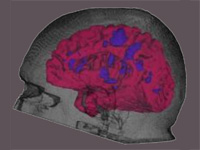

Integrative Visualization of Temporally Varying Medical Image Patterns

We present software for the visualization of temporal changes of disease patterns using stacks of medical images collected in time-series experiments. With this software users can generate 3D surface models representing disease patterns and observe changes over time in size, shape, and location of clinically significant image patterns. Statistical measurements of the volume of the observed disease patterns can also be obtained simultaneously.

(journal article, online article @JIB, reference).

Generation of Connectivity-Preserving Surface Models of Multiple Sclerosis Lesions

In this article we introduce a software tool to build 3D surface models of Multiple Sclerosis (MS) brain lesions from 2D image stacks typically obtained through Magnetic Resonance Imaging (MRI). This tool allows users to create 3D models of MS lesions quickly and visualize the lesions and brain tissue using various visual attributes and configurations.

(journal article, online version @ google books, online version @ SHTI, reference).

A Novel MRI Visualization Tool for White Matter Pathology in Multiple Sclerosis

We developed a tool to visualize MS lesions and their 3D surface models to show changes in the lesions over time. These can be shown as an animation to elucidate differences across scanning sessions. With this software, a volumetric sub-region can be selected from the 3D model for zooming or animation, and a point on the 3D model can be selected to highlight all lesions connected to it. The total volume of lesions can be calculated, displayed as a chart, and exported.

(poster, online abstract @ SfN, reference).

Concurrent Visualization of and Mapping between 2D and 3D Medical Images for Disease Pattern Analysis

We present a software tool to highlight and display regions of interest in 2D medical images and their 3D mesh model counterparts. This tool can help researchers visualize and compare brain lesions and tissues in 2D and 3D at the same time.

(conference article, online article @ VBL, reference).